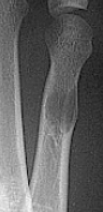

Describe what has happened at the shaft of the 3rd met | Exuberant periosteal new bone production. May have resulted if a stress fracture was not treated and the patient continued weight bearing activities. |